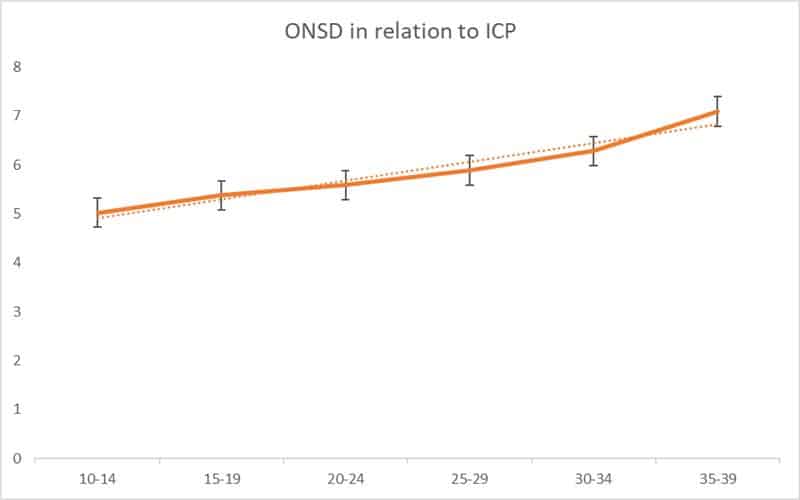

Radiology | Jan 06, 2025

Measurement of Optic Nerve Sheath Diameter as a Determinant of Increased Intracranial Pressure Among Stroke Patients in Southwestern Nigeria

Background: Elevated intracranial pressure (ICP) is a critical factor contributing to morbidity and mortality in stroke patients, emphasizing the need...Read More